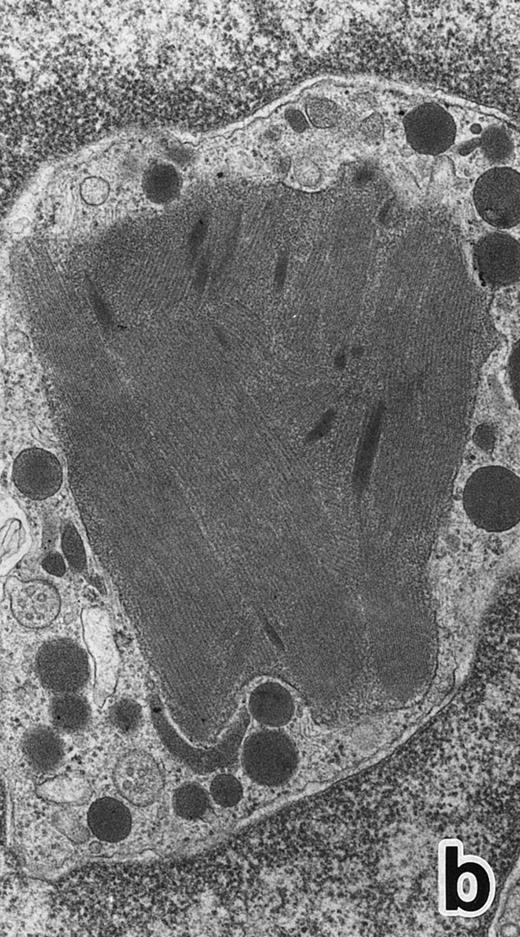

After 2 to 3 weeks of ATRA treatment, maturation of leukemia cells progressed further, and cells resembling normal PMNs appeared (Fig 5). These cells contained multilobulated nuclei with marginally condensed heterochromatin and glycogen particles, characteristic of normal mature neutrophils. rER and free ribosomes became rare as the maturation process proceeded. However, these cells were still rich in primary (type I) granules, which somewhat varied in size and shape, including small and/or elongated forms. A small number of ellipsoid type II primary granules with a nucleoid structure were occasionally observed in patients no. 1 and 2, but not in patient no. 3. Conversely, MPO-positive, small, possibly type III, primary granules were rarely observed intermingled among the larger primary granules in maturing neutrophils in patient no. 3 alone. Despite the ultrastructural features otherwise characteristic of normal mature PMNs, specific granules, which are electron-lucent, elongated or dumbbell-shaped small granules, were not present in the majority of these PMN-like cells, as clearly shown by electron-microscopic cytochemical staining for MPO (Fig 5). The cells contained only MPO-positive primary granules and no MPO-negative secondary granules. A few abnormal primary granules, including Auer rods or C-H type granules, were still present in some cells, and these cells too were consistently devoid of specific granules (Fig 6). Another unusual finding in PMN-like cells at this stage was the presence of large spherical lipid droplets (Fig 5a), which may indicate altered physiological metabolism in these cells,29 because lipid droplets are usually not seen in normal PMNs. Although few in number, PMNs having both primary and secondary granules were also observed (Fig 7), and less mature intermediate forms with indented single nuclei or irregularly lobulated nuclei and numerous primary granules were still present at this stage of ATRA treatment.

(a) A PMN in patient no. 1 that appeared in the bone marrow after 3 weeks of ATRA treatment. There are numerous granules in the cytoplasm, including spherical, elongated, and even dumbell-shaped granules, all of which are MPO-positive, ie, primary granules. A lipid droplet (L) is also present. (MPO-stained section, original magnification × 15,200.) (b) Higher magnification of a portion of the cytoplasm in (a). MPO-negative secondary granules are not seen. (MPO-stained section, original magnification × 30,900.)